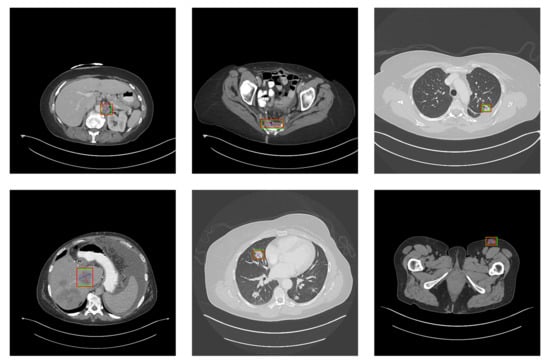

5.2. Detection Results

For further comparison, we extracted six images from the CT image series of DeepLesion. These images were taken from different sites of lesions and different areas of lesions, showing the detection results of the comparison model as comprehensively as possible. Figure 10, Figure 11, Figure 12, Figure 13, Figure 14, Figure 15, Figure 16, Figure 17, Figure 18 and Figure 19 show the detection results. All green boxes represent ground truth; red boxes denote predicted bounding boxes. It can be seen that Faster-RCNN performs very poorly on small lesions and lesions that are not easy to identify, while YOLO v3, YOLO v4, and SSD series perform relatively well. However, the aspect regression of the bounding box at small lesion locations is still not accurate. On the other hand, EfficientDet, Mask-RCNN, and YOLO v5 perform relatively well and detect lesions accurately. This may be related to the attention extraction module in these networks.

Figure 15.

The detection results of EfficientDet in the DeepLesion dataset. The green box marks the location of the lesion.

Figure 16.

The detection results of SSD 300 in the DeepLesion dataset. The green box marks the location of the lesion.

Figure 17.

The detection results of SSD 512 in the DeepLesion dataset. The green box marks the location of the lesion.